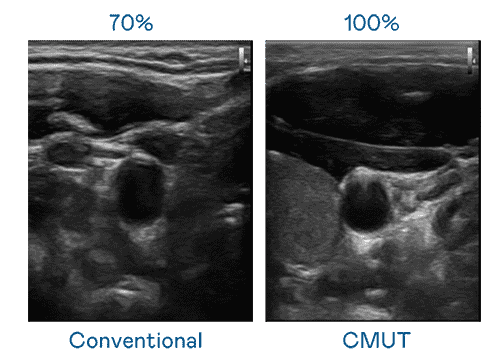

CMUT 技术是一种用电容式微机电元件来产生超音波讯号的技术。。与传统 PZT 压电式技术相比,,,,CMUT 频宽增加 30%,,,,更宽频的超音波讯号让影像解析度大幅提升,,是实现高影像品质医疗超音波扫描、、促进精准医疗发展的关键技术。。

超音波影像的解析度高低,,首先取决于探头能发出的讯号频宽。。。28国际 CMUT 可提供高清晰的超音波讯号,,,,提供高频宽、、高灵敏度、、影像纹理细节更高的超音波影像,,协助医护人员缩短影像判读时间及利用精准的医疗影像进行诊断。。。